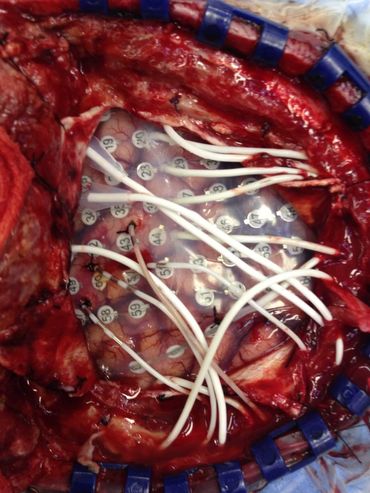

Understanding Brain Surgery: A 2013 Experience

Axial MRI scan showing detailed brain structures including eye sockets and brain tissue.